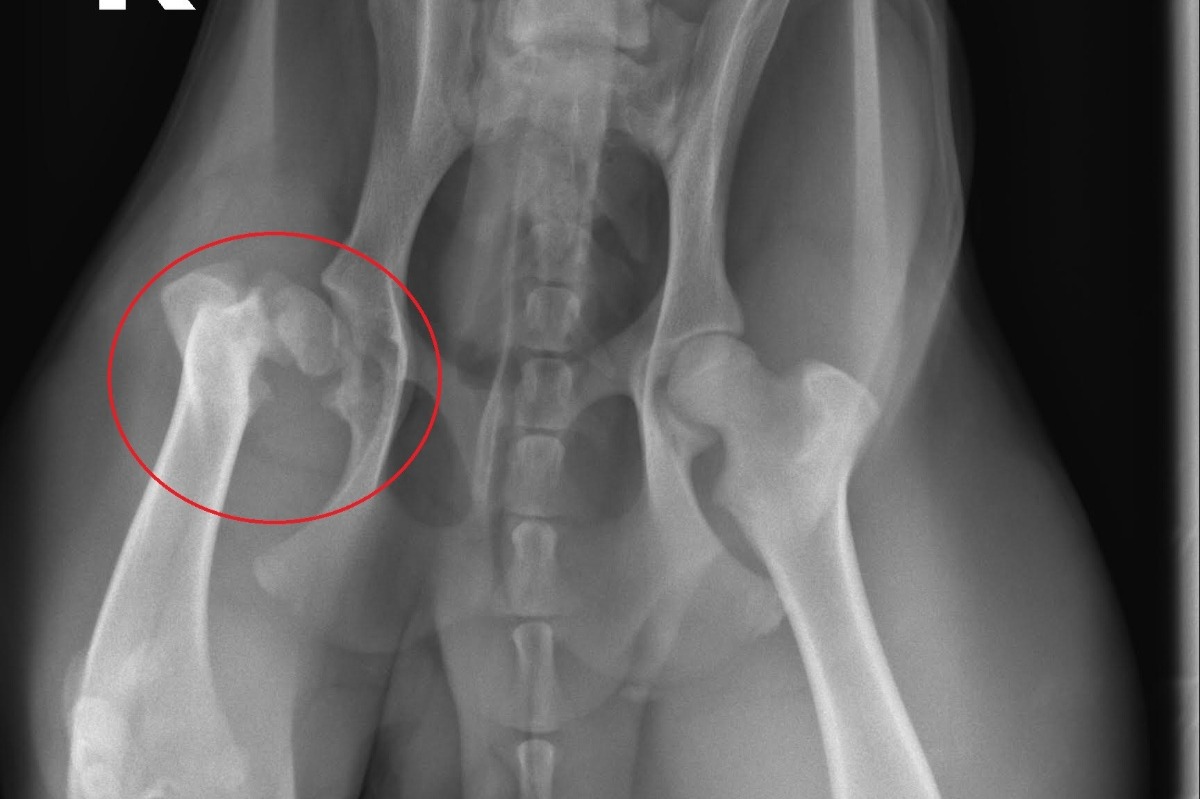

About a year and a half have gone by and his femur/hip injury seemed to have worked itself out. This past summer he was running and jumping and going on countless outdoor adventures with me, with no sign of any sort of lameness in his leg. The past month, however, has been a different story. When he is outside, he hides his pain well but has developed a very noticeable gait in his walk. Inside, when he is not being stimulated or distracted by anything he does not put any pressure on his leg and has been limping almost constantly. His right leg has developed severe muscle loss from not having pressure put on it. I brought him to the vet on 12/30/20 and spoke to a surgeon at VSEC. After acquiring new X-Rays it was revealed that on top of the fracture, he now has a large loose bone fragment present and osteoarthritis in his right leg.

The surgery he needs is called a Femoral Head Osectomy ( FHO). In short, the surgeon will reshape Waylon's femoral head or the ball of his femur, so it fits properly in his hip. Although he will have a sort of, cowboy strut, after the surgery due to his right leg essentially becoming slightly shorter, he will have full mobility again. VSEC has also told me also that Waylon has bilateral patella luxation or trick knees. His right knee is slightly worse than his left and before X-Rays, I was initially told he would need surgery on his knee as well, but the X-rays revealed the luxation was not too severe and surgery wasn't needed. However, Dr. Round at VSEC graciously offered to "tighten" up his right knee joint while he is under the knife for his hip. So young Waylon will get a two for one special from the awesome vets at VSEC and will be back to his old self again shortly after surgery.